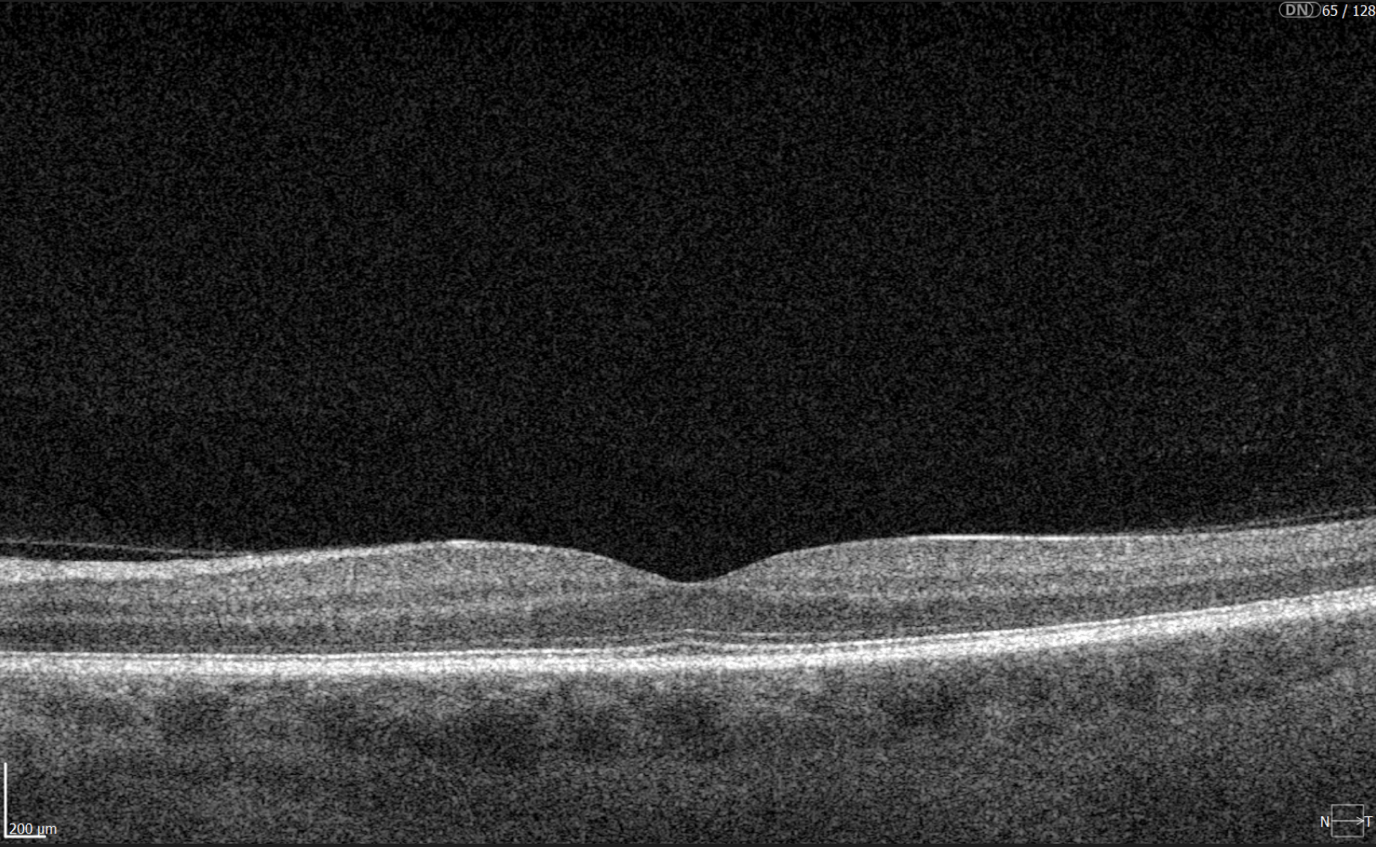

Diabetic retinopathy screening OCT

Diabetic retinopathy (hyperreflective foci, moderate destruction of the ellipsoid zone and RPE), diabetic macular edema (neuroepithelium edema, intraretinal cystic cavities), epiretinal membrane